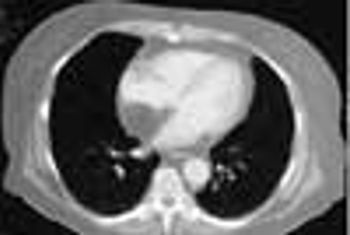

An 80-year-old man with a history of congestive heart failure, coronary artery disease, cardiomyopathy, and thoracic and abdominal aneurysms was taken to the emergency department because of mental status changes, back pain, and ecchymotic areas over his body. The ecchymoses started on his back 5 days before admission and spread to his abdomen.